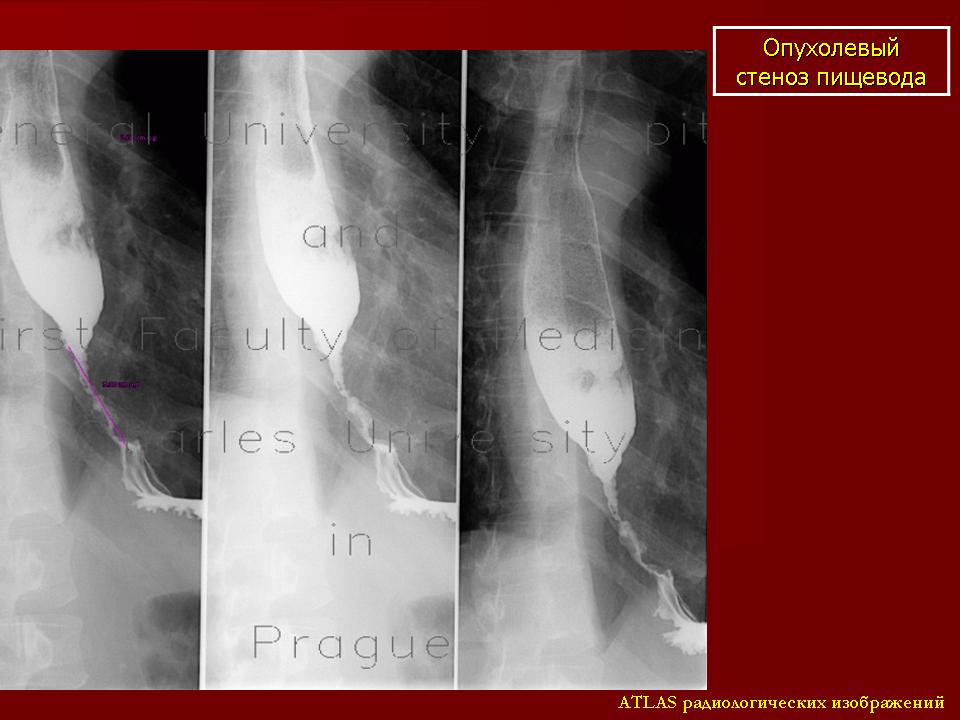

Опухоли пищевода, дифференциальная диагностика. Двойное контрастирование и компьютерная пневмоэзофаготомография. Атлас. Бодров Ю. Д. Нестеренко С.Ю.

Рентгенологическое исследование. Двойное контрастирование(ДК).

Метод ДК долгие годы считавшийся дополнительно отнесен в разряд основных; позволяет одновременно изучение контуров, рельефа слизистой оболочки, эластичности стенок пищевода(ригидности), точной локализации и размеров патологических изменений, характера роста опухолей, что облегчает дифферинциальную диагностику с другими заболеваниями и осложнениями, давление из вне на пищевод.